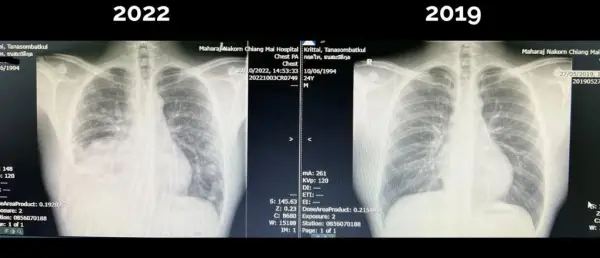

โพสต์ที่สอง ได้เผยแพร่ผลเอกซเรย์ปอด เปรียบเทียบระหว่างปี 2562 กับ 2565 พบว่าปอดด้านขวาหายไปครึ่งหนึ่ง มีก้อนขนาดใหญ่ถึง 8 เซนติเมตร และมีน้ำในปอดร่วมด้วย นอกจากนี้ยังมีก้อนเล็กๆ ในปอดด้านซ้ายอีกหลายก้อน และด้านขวาบนเช่นกัน ทั้งที่ก่อนหน้านี้ยังไปเล่นบาสเกตบอลได้ แม้ช่วงหนึ่งเดือนที่ผ่านมาความฟิตลดลงก็ตาม โดยพบว่าเป็นมะเร็งปอดระยะลุกลาม

โพสต์ที่สาม สาระสำคัญโดยสรุปก็คือ ตนเป็นมะเร็งปอดระยะลุกลาม ไม่สามารถผ่าตัดเอาก้อนออกแล้วหายขาด ซึ่งตนสงสัยว่าเกิดขึ้นได้อย่างไร เพราะดูแลสุขภาพสม่ำเสมอ แต่พบว่ามีอาการไอ ทั้งไอแบบมีเสมหะและไอแห้ง แม้จะตรวจโควิด-19 ก็ไม่พบเชื้อ จึงเริ่มรักษาอาการกรดไหลย้อนก่อน ระหว่างนี้สามารถเล่นกีฬาได้ตามปกติ ทำงาน ใช้ชีวิตได้ตามปกติ กระทั่งเมื่อวันที่ 3 ต.ค. ที่ผ่านมา ซึ่งไม่มีตารางงาน จึงได้ไปตรวจสุขภาพ พบว่า ฟิล์มที่ปอดข้างขวา เหลืออยู่ครึ่งเดียว ลักษณะเหมือนมีก้อนกับน้ำอยู่ในปอดด้านขวา และปอดด้านซ้ายก็มีก้อนเล็กๆ เต็มไปหมด

หลังจากผ่านการตรวจทุกอย่างมาแล้ว ทั้งเอกซเรย์คอมพิวเตอร์ ผ่าตัดเพื่อนำชิ้นเนื้อมาตรวจ ตรวจคลื่นแม่เหล็กไฟฟ้าที่สมอง พบว่าเป็นมะเร็งปอดระยะสุดท้าย โดยตัวก้อนหลักขนาดเกือบ 8 เซนติเมตร ที่ปอดด้านขวา นอกจากนี้ ตัวมะเร็งยังมีการกระจายไปที่เยื่อหุ้มปอด และปอดข้างซ้ายอีกหลายจุด และกระจายไปที่สมองถึง 6 ก้อนด้วยกัน แต่ละก้อนมีขนาดใหญ่ โชคดีที่ไม่มีอาการทางสมอง พร้อมกันนี้ได้ขอบคุณอาจารย์ที่ให้ความช่วยเหลือ ทั้งการผ่าตัด การได้รับ chemotherapy Immunotherapy และได้รับการฉายแสงที่ศรีษะทันทีที่เจอก้อน